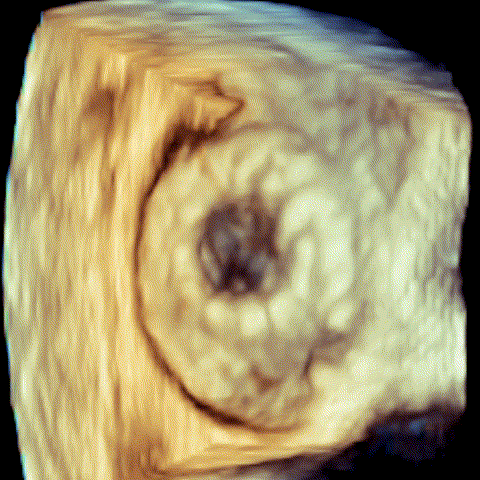

病例1 三维超声 病例1 三维超声

(瓣中瓣植入前) (瓣中瓣植入后)